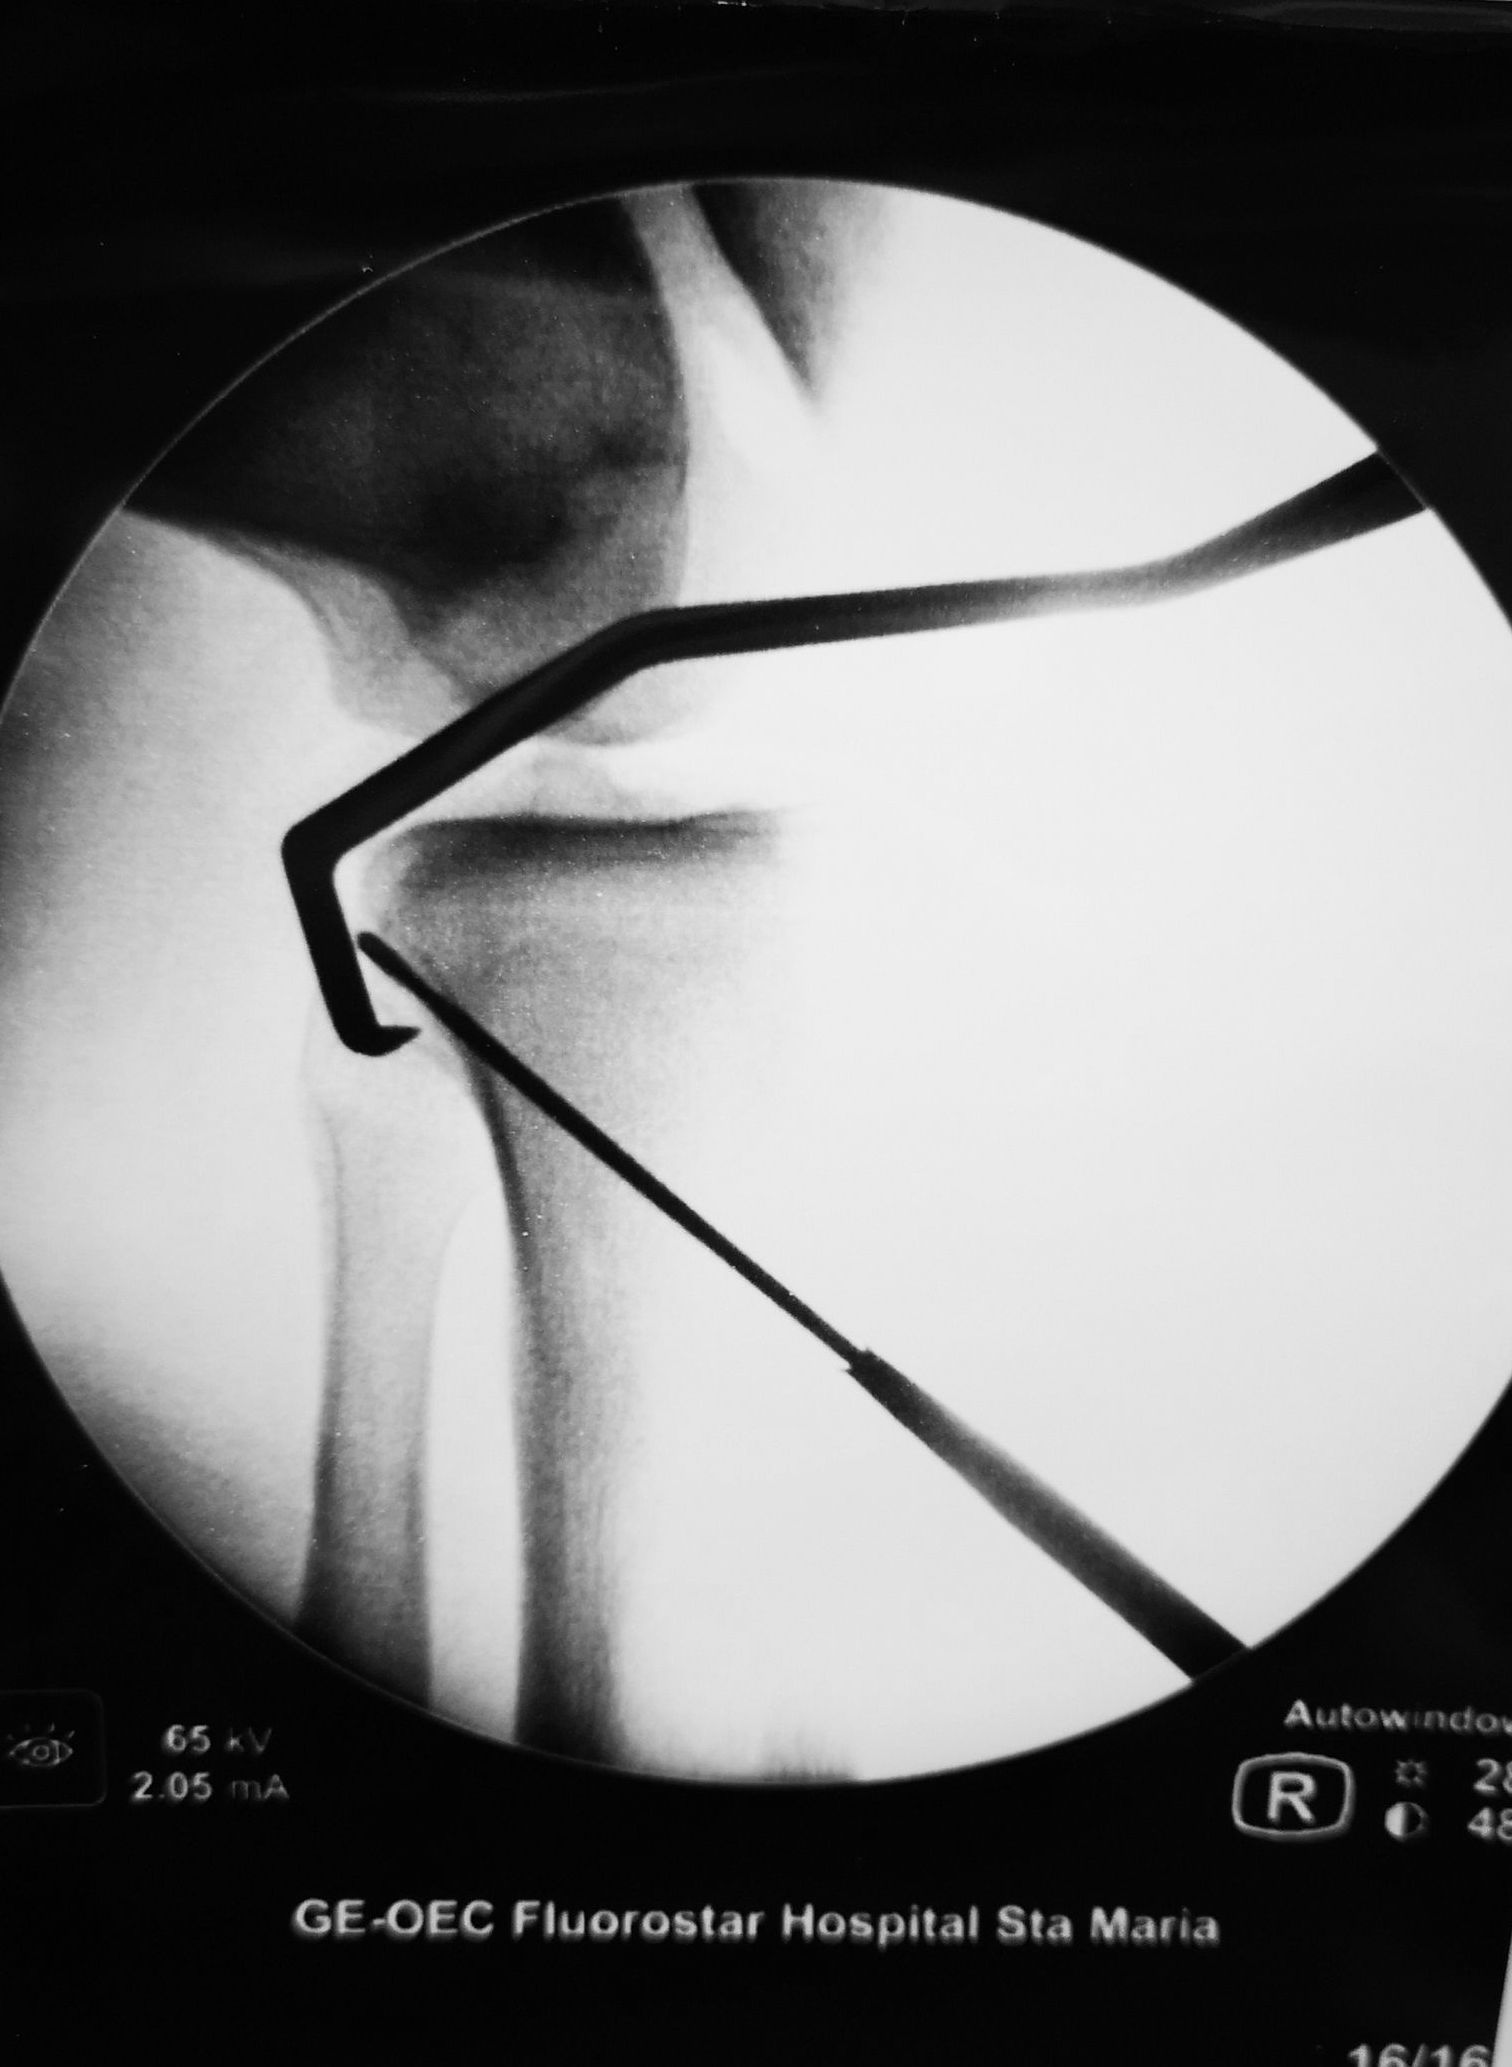

Cirurgia Artroscópica

Patologia do Tornozelo